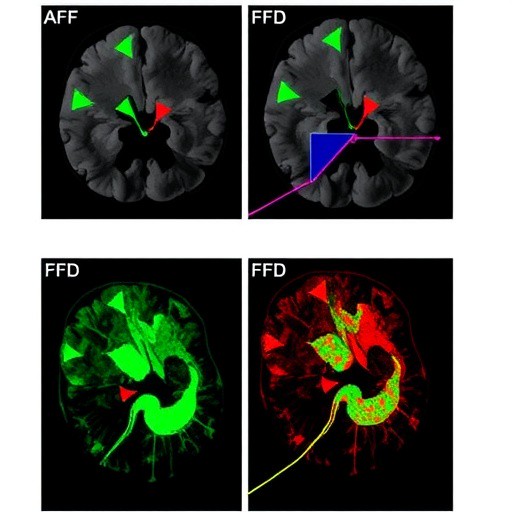

In a groundbreaking advancement in the fight against glioblastoma, a recent study reveals the promising potential of targeting fibroblast growth factor receptors (FGFRs) to enhance the effectiveness of tumor treating fields (TTFields). This innovative research opens a new therapeutic avenue that could significantly improve outcomes for patients diagnosed with one of the most aggressive and treatment-resistant brain cancers. Glioblastoma stem cells (GSCs), notorious for their resilience and ability to propagate tumors, are particularly susceptible to this combined approach, signaling a hopeful shift in therapeutic strategies.

Using sophisticated in vitro and in vivo models, the study demonstrated that FGFR inhibition effectively diminished glioblastoma stem cell viability and enhanced their susceptibility to TTFields-induced mitotic disruption. The dual strategy resulted in increased apoptotic rates within GSC populations compared to treatment with TTFields or FGFR inhibition alone. This additive effect emphasizes the potential synergy between molecular targeting and physical disruption approaches, paving the way for more comprehensive glioblastoma therapies.

At the molecular level, FGFR blockade appeared to interfere with key downstream signaling cascades, notably the PI3K/AKT and MAPK/ERK pathways, which are critical to cell survival and proliferation. This interference led to impaired cell cycle progression and heightened sensitivity to the mechanical stresses imposed by TTFields. Furthermore, the dual treatment reduced markers of stemness within glioblastoma populations, suggesting a direct impact on the tumor-initiating cell compartment that is often responsible for recurrence.